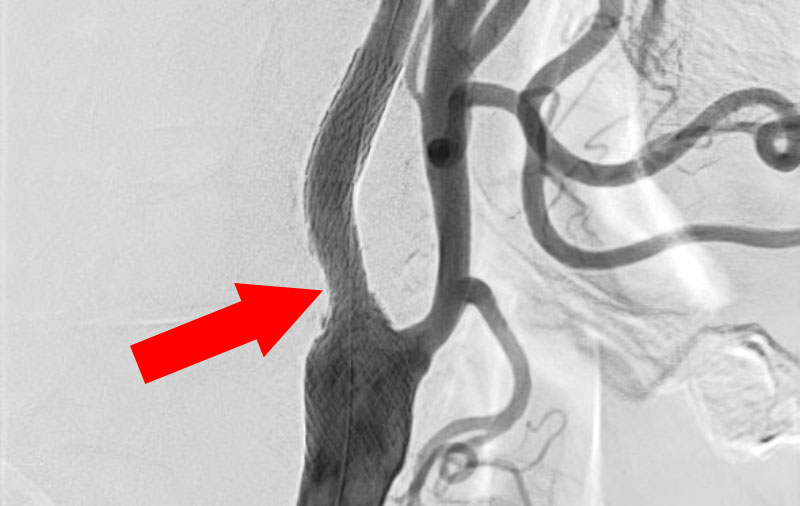

1346

'23年2月20日

右頚部内頚動脈狭窄症

80代

大阪府の病院

手術写真

治療

前

'23年2月